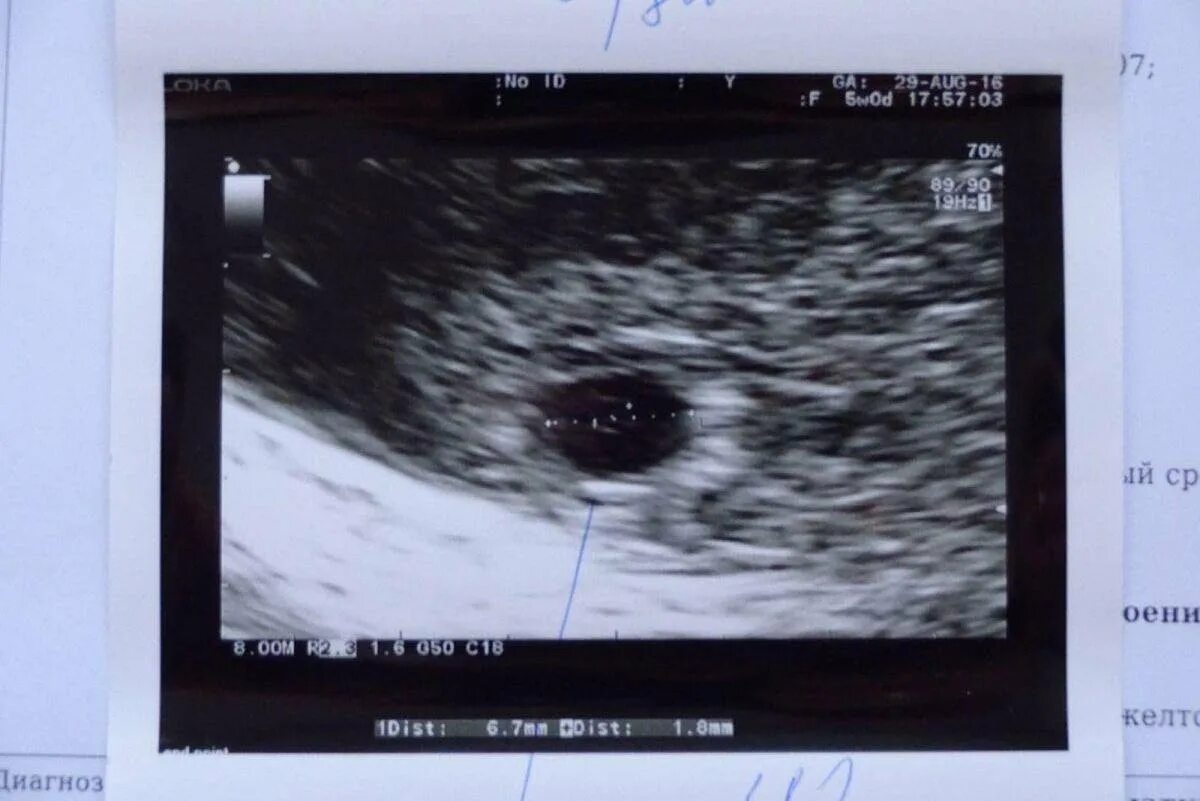

Узи 6 месяцев